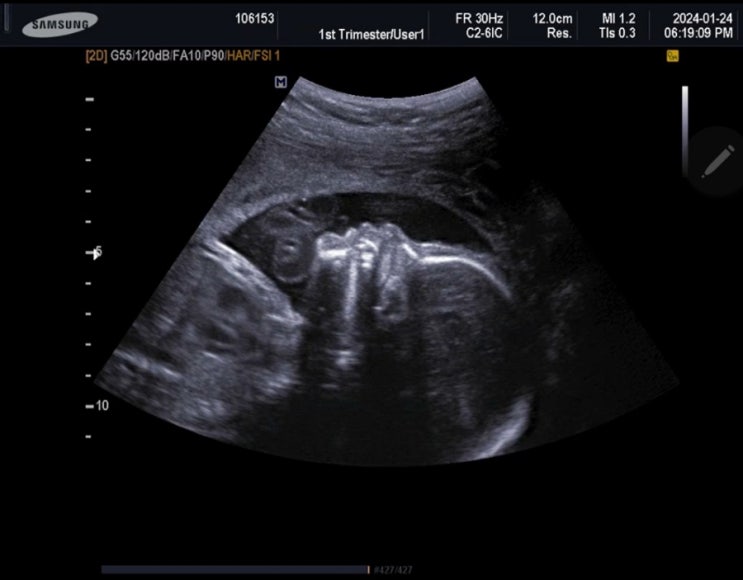

임신28주. 작은아기

28주4일. 1044g ... 둘째는 35주차 조산이었음에도 2.6kg으로 니큐한번 안들어가고 건강했는데.. 우리셋째....

"아기가 거꾸로 있으면(역아) 몸무게가 더 작게나와요" 내 담당의는 왜 이 이야기를 안해주셔서....